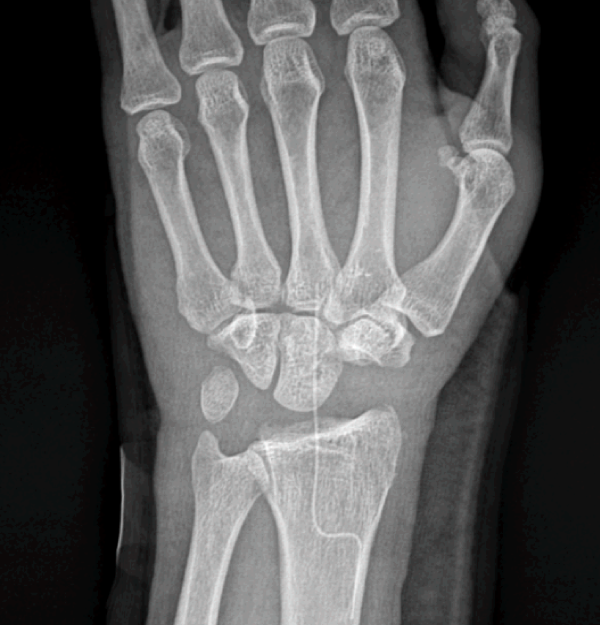

주상월상인대파열 MRI영상